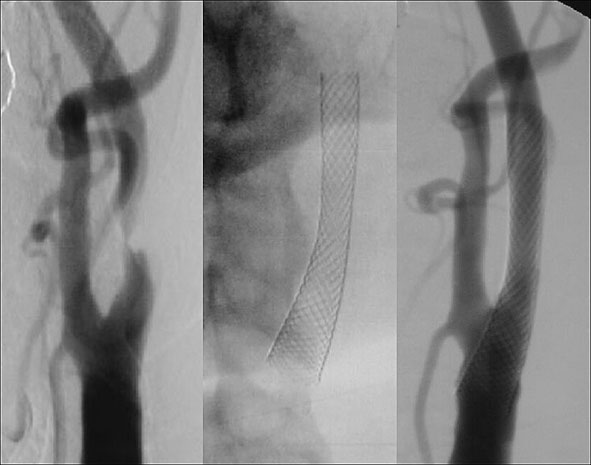

• Carotis-Stents und aller Kopf-Hals-Gefäße